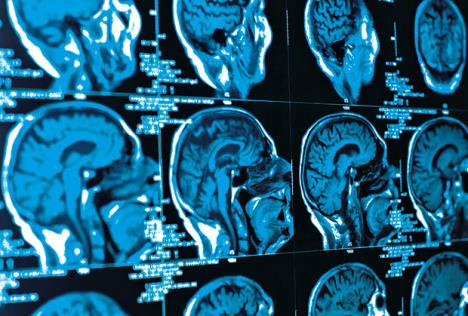

Uzrok afazije je poznato ili nepoznato moždano oštećenje (oštećenje koje je minorno, tj. molekularno ili neurobiohemijsko, pa je morfološki nevidljivo, odnosno ne može se dokazati dijagnostičkim postupcima). Najčešći uzrok afazija je moždani udar. Uzroci su obično vaskularne lezije, tumori, traume, degenerativne bolesti CNS-a. Može nastupiti i povredom glave, udarcem ili infekcijom.

Afazija je nesposobnost upotrebe jezika: kao takva, ona se manifestuje kroz sve jezičke modalitete: pogađa sposobnost slušanja i govora, čitanja i pisanja, a ne zavisi od sluha i vida.